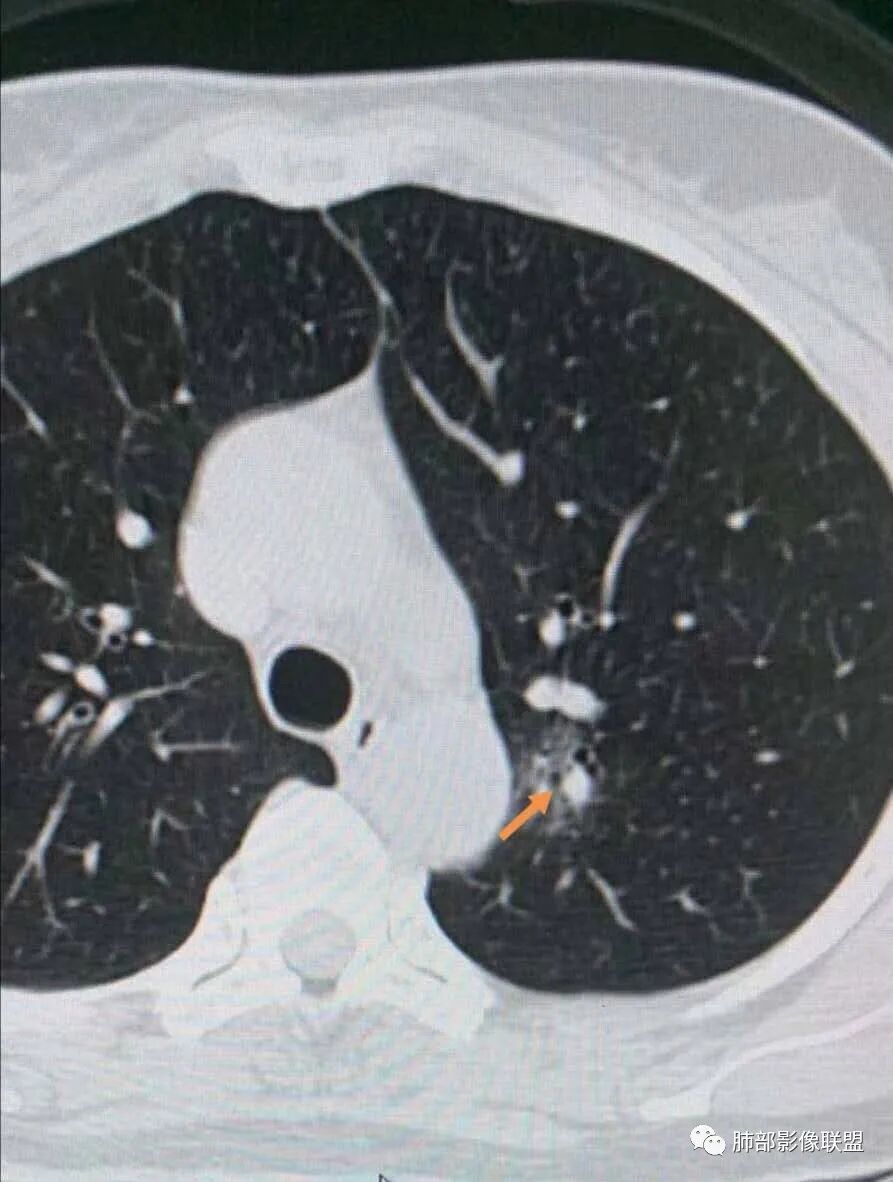

一、先讨论GGN吧

1、密度?MGGN?PGGN?

2、边界?清?不清?

3、有无收缩力?有胸膜牵拉?毛刺?

4、血管连通 移动:3型?4型?

两条都进入,相互交通-4

常规判断还需要大小、CT值

大家诊断啥?

IAC>MIA

MIA

微浸润腺癌

为啥不是原位?

有收缩,牵拉

血管进入增粗,胸膜牵拉

有月牙 两条都进入,相互交通-4 胸膜牵拉

不是纯的GGO

血管进入

二.左肺上叶前段磨玻璃结节:

该结节较大,边界清楚,小叶间隔阻挡特征相当明显,微浸润腺癌的诊断几乎没有争议!